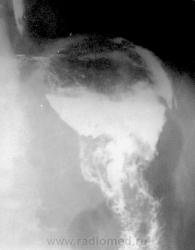

Третья гравюра демонстрирует затёк контраста из толстой кишки куда-то во внеорганное пространство…, жаль, фрагмент картины маловат.

Третий - ирригоскопия, после опорожнения.